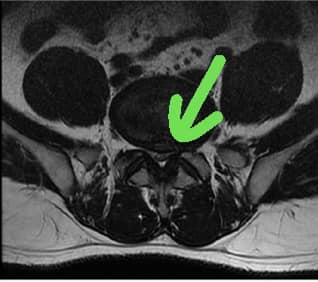

1.L5S1椎間盤退化

2.L4L5 巨大椎間盤脫垂

💪溝通:片子上看起來突出非常巨大而且往椎管下脫垂,患者說沒有大小便失禁的症狀,也沒有大小便疼痛,也沒有垂足跟腳萎縮情況,估計脊髓沒損傷,只是突出的椎間盤壓迫神經根導致,安排四次治療看效果如何,如果有改善就繼續治療,如果還是麻就建議開刀